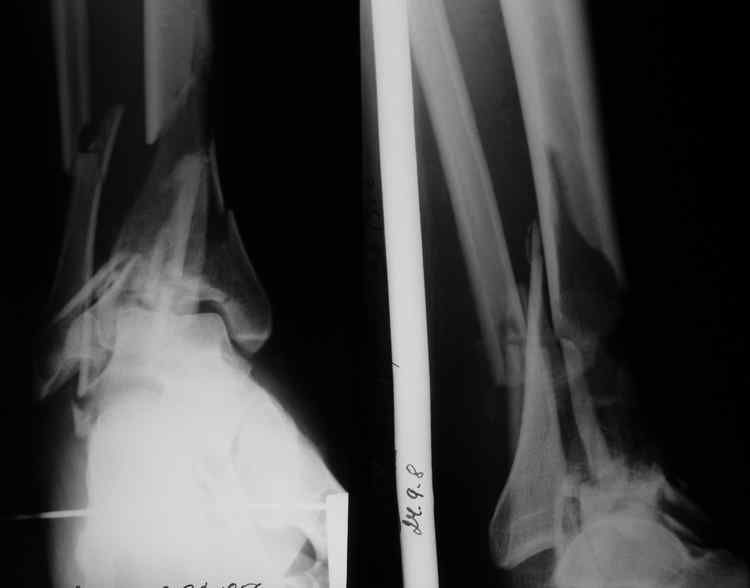

[Ortho] Тяжелый перелом пилона

Прошу высказать мнение по поводу лечения перелома голени. Мужчина 54 года, травма 24.09.08. Перелом закрытый.